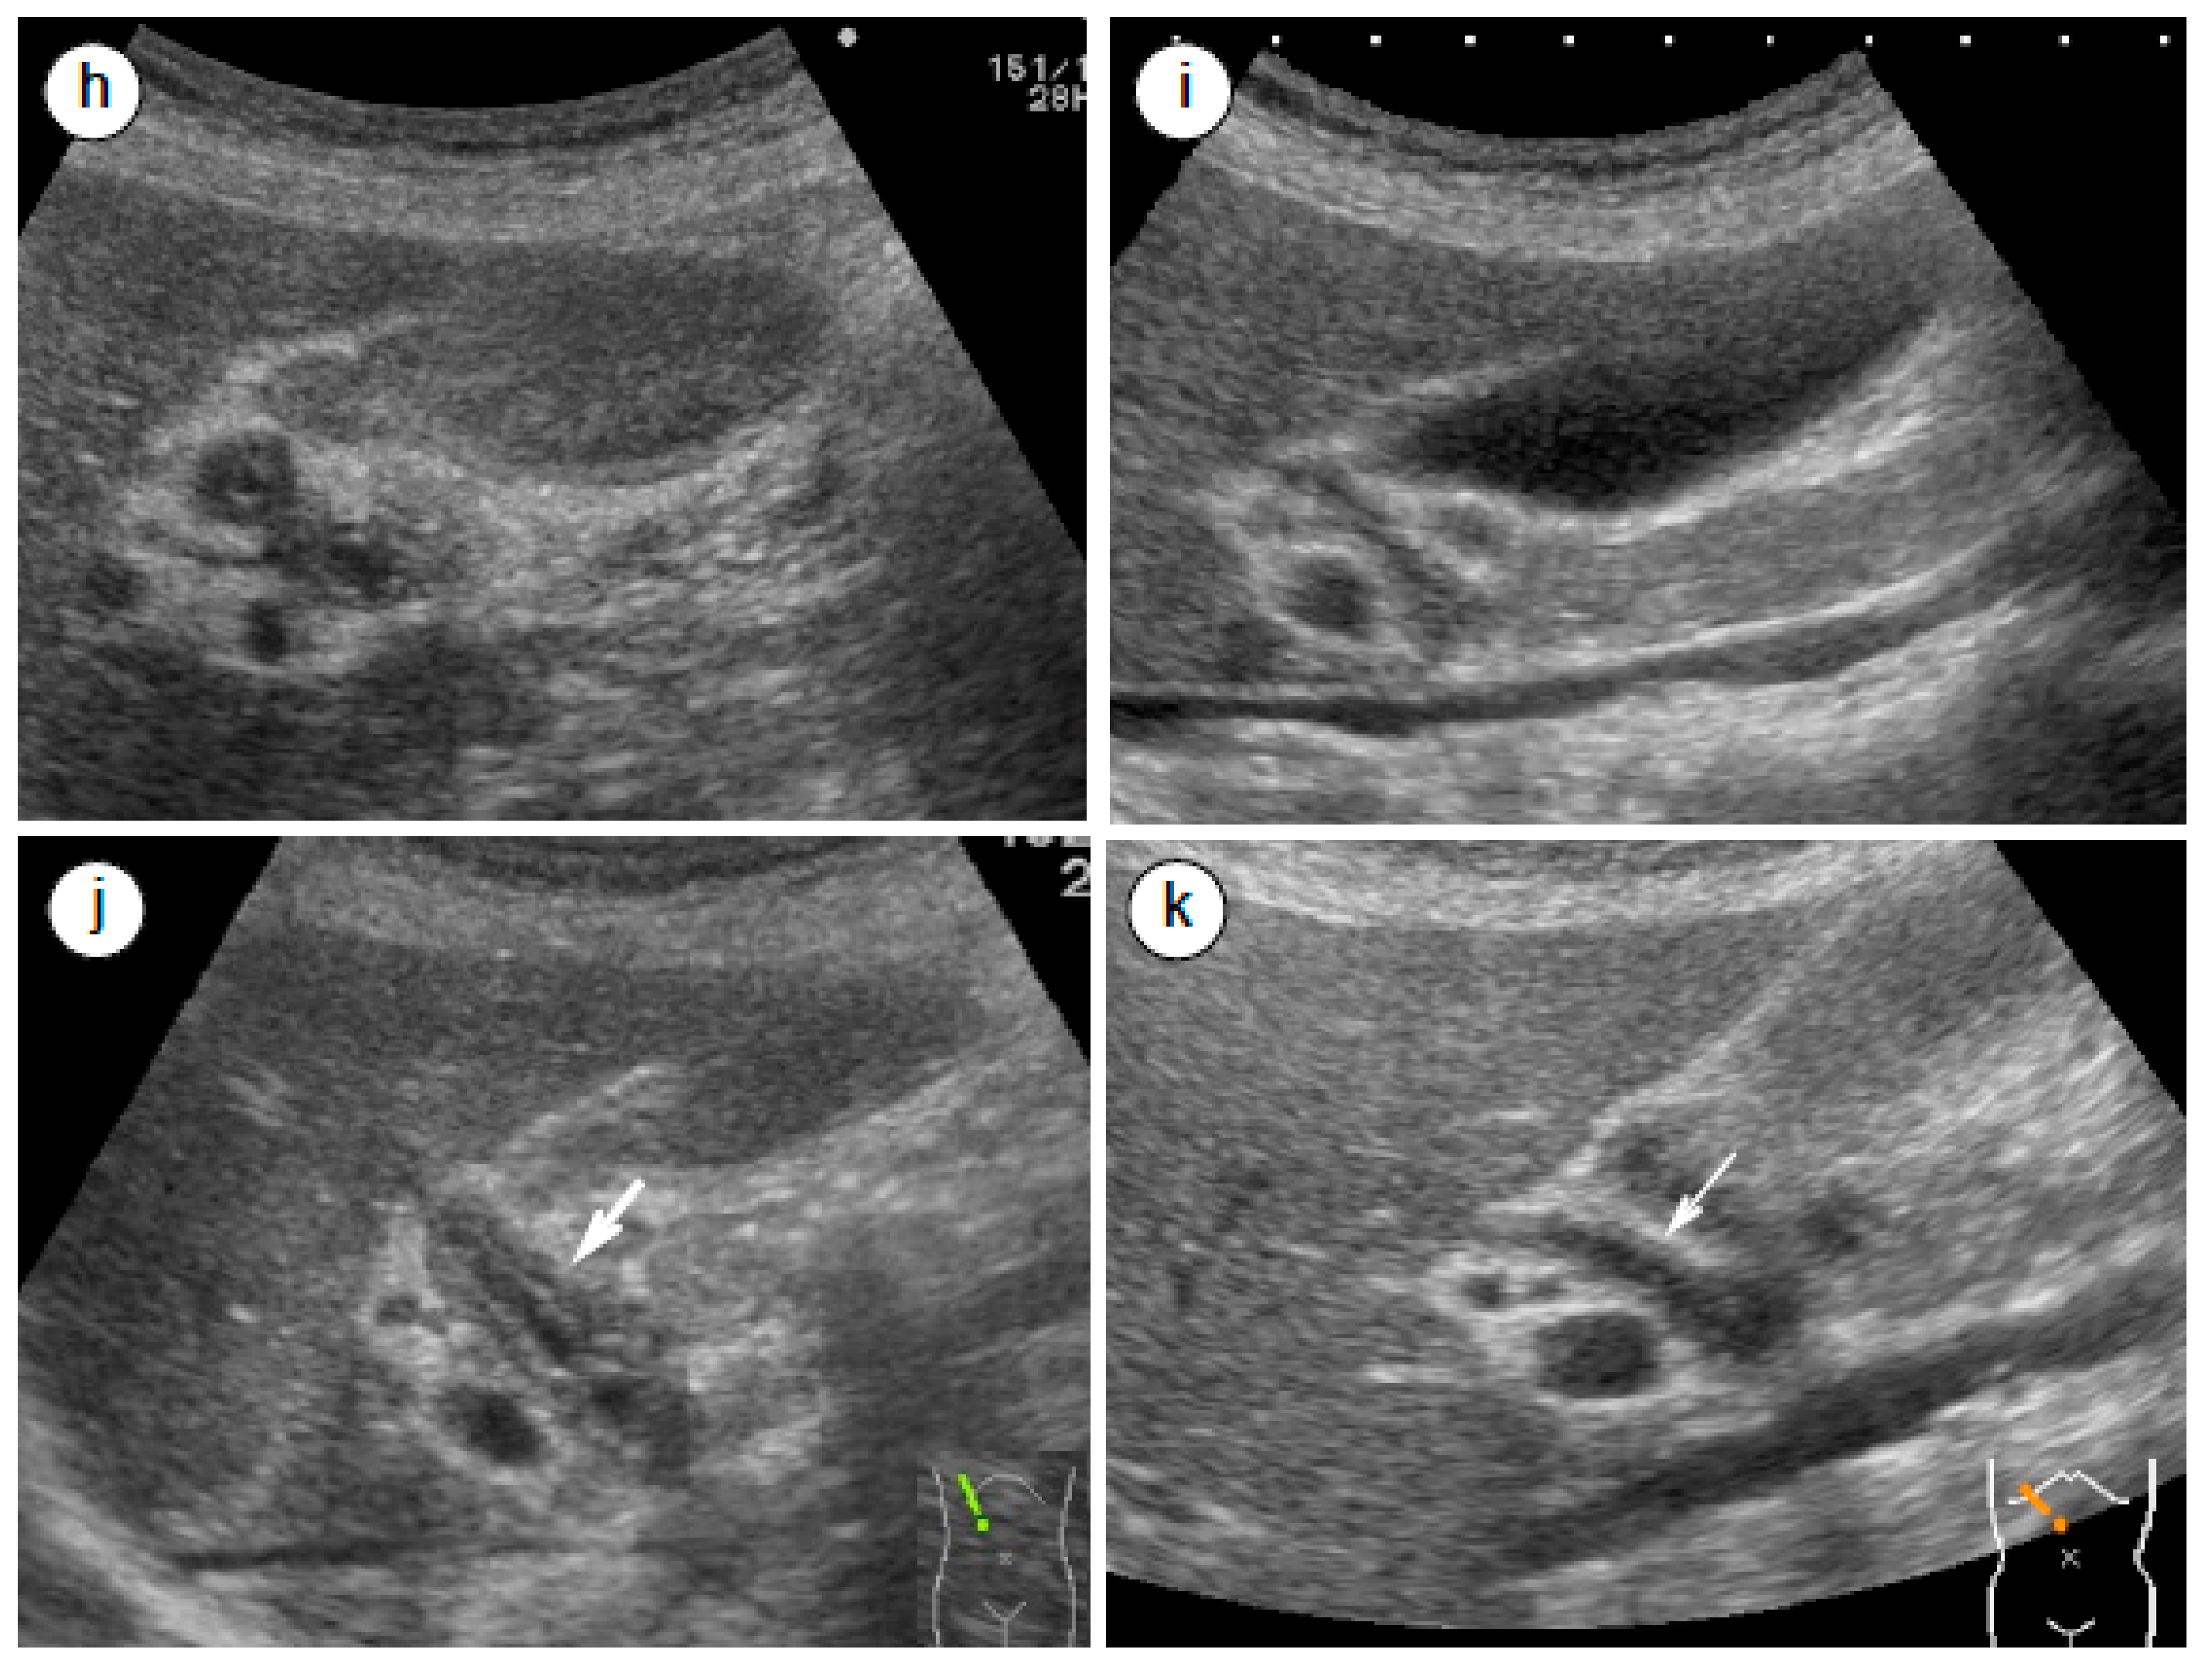

- Matsubayashi, H.; Yoneyama, M.; Nanri, K.; Sugimoto, S.; Shinjo, K.; Kakushima, N.; Tanaka, M.; Ito, S.; Takao, M.; Ono, H. Determination of steroid response by abdominal ultrasound in cases with autoimmune pancreatitis. Dig. Liver Dis. 2013, 45, 1034–1040. [Google Scholar] [CrossRef]